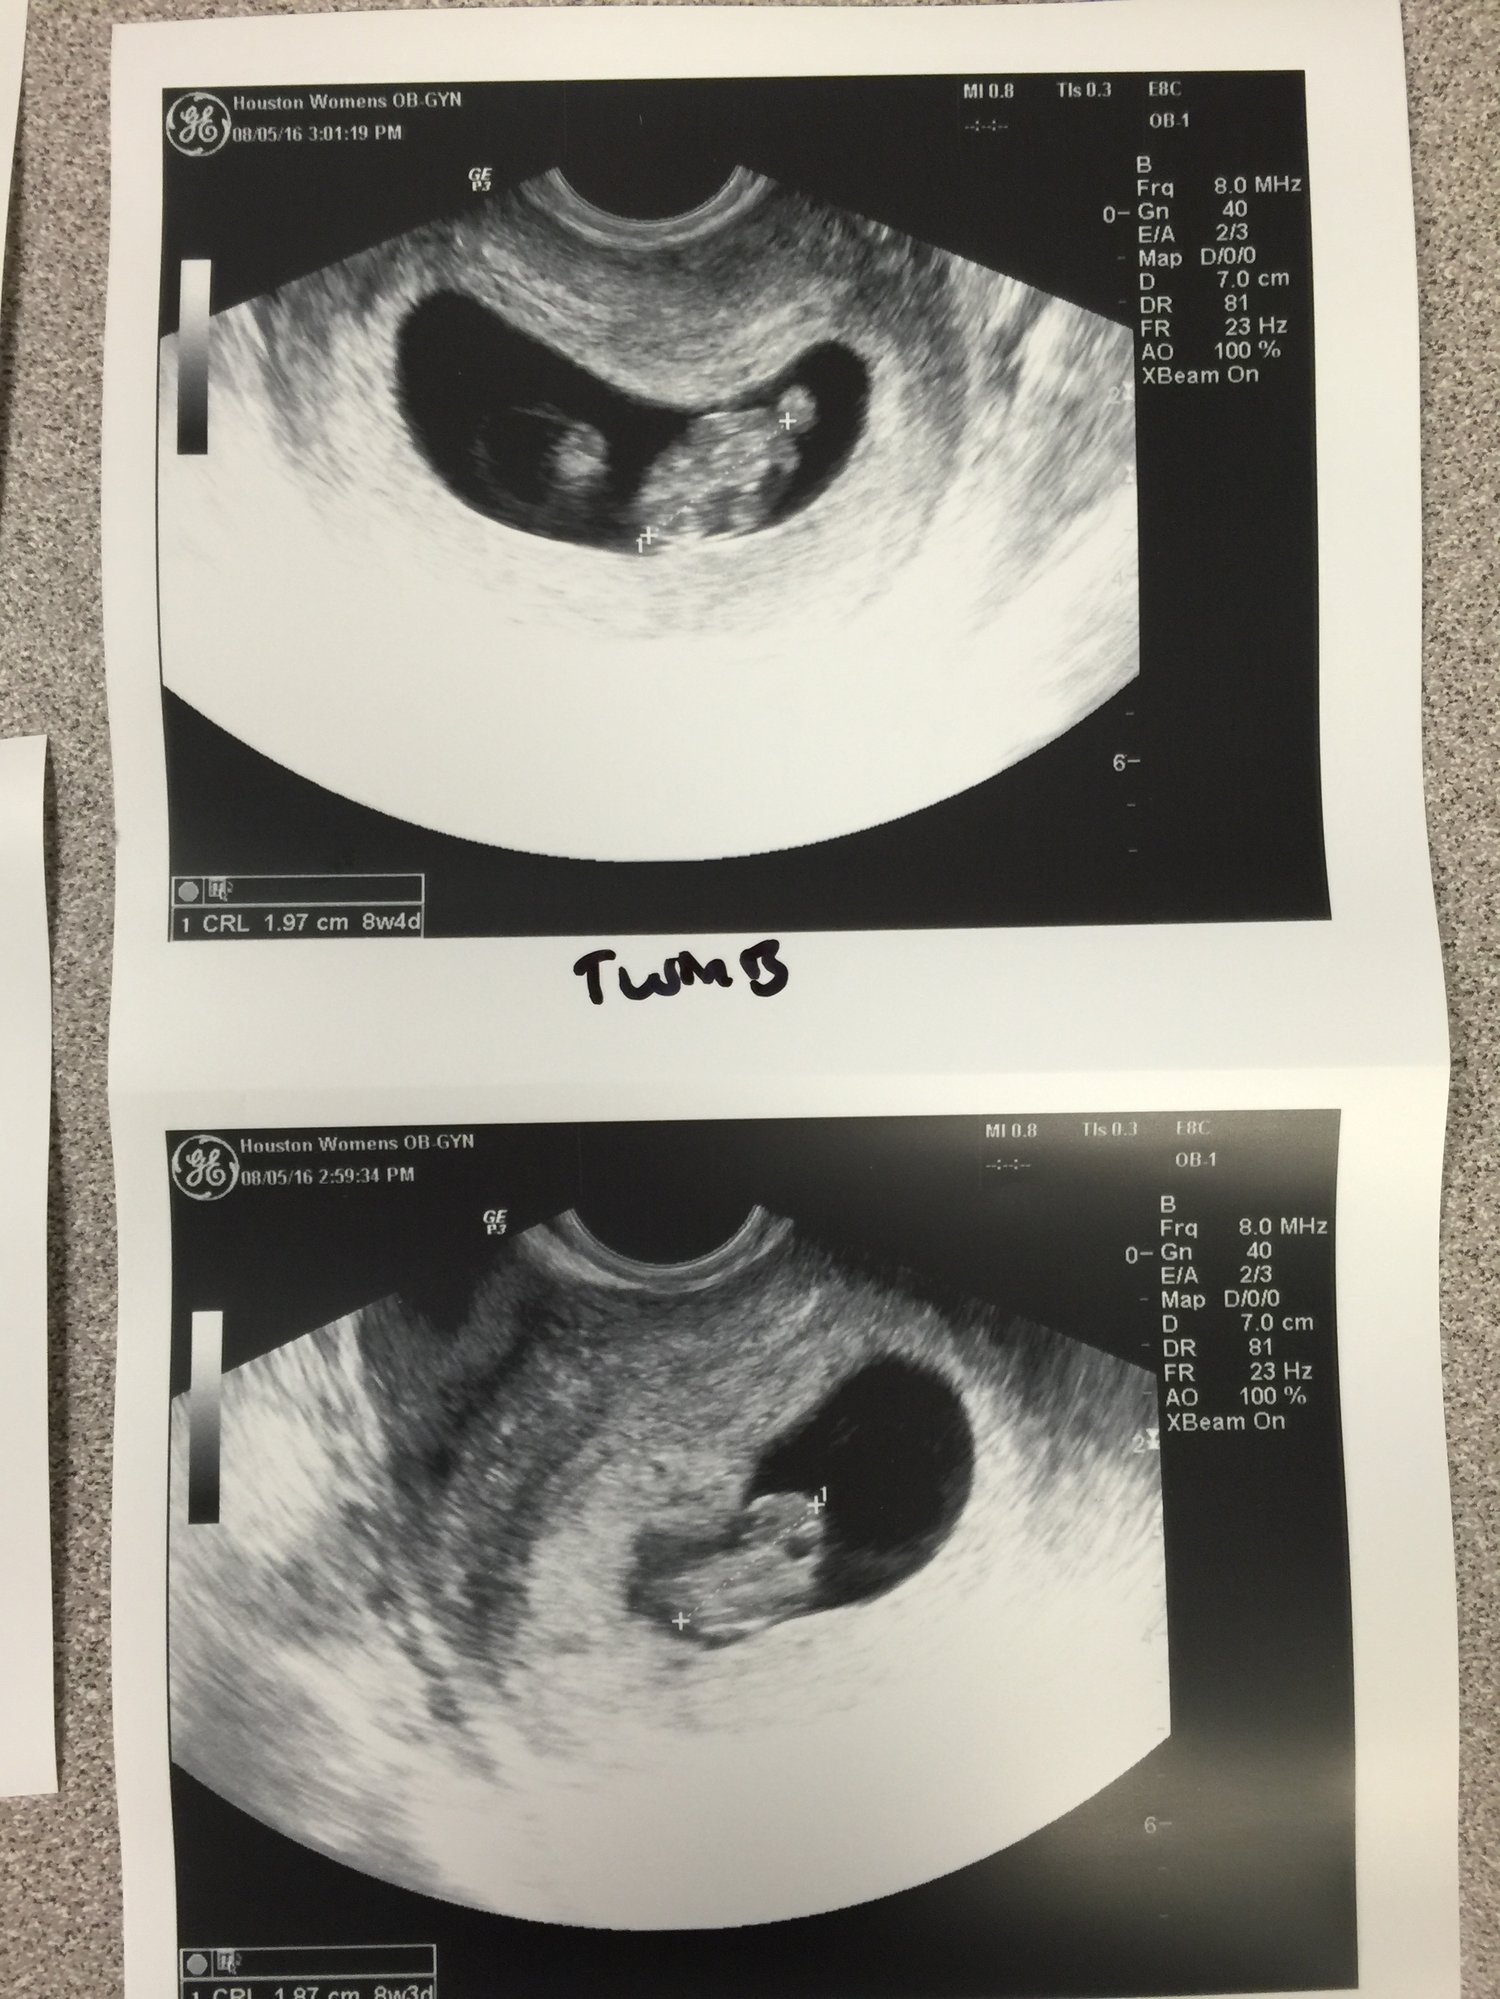

update: so my high risk obgyn (which is going to be the consultant to my regular obgyn) performed an ultrasound last Friday with a better machine. babies are doing great. however she thinks they are smaller than LMP by 5-7 days, ( so a little over 7 weeks instead of a little over 8 weeks) due date still in march though. maybe I ovulated later? but they are good sizes, good heart beats. and she thinks they are mono-di. which is good. but now I have to worry about other stuff like twin on twin transfusion.

Had aother ultrasound today! Babies are measuring 9 weeks and growing good they really think they are mono di now. And one of them is sideways. So 3 pix. One is twin a and b seperate and the one with them together but not in the same position. U only see the side head viewish. Strong heart beats 179 and 181 *grow grow babies grow grow* doing the genetics blood test next week which, since they are identical, should tell us the gender! Yay

i was all worried going in, and got so emo when I heard their heart beats as always. The little nubs for hands and legs are there. One of them was wiggly a little too!